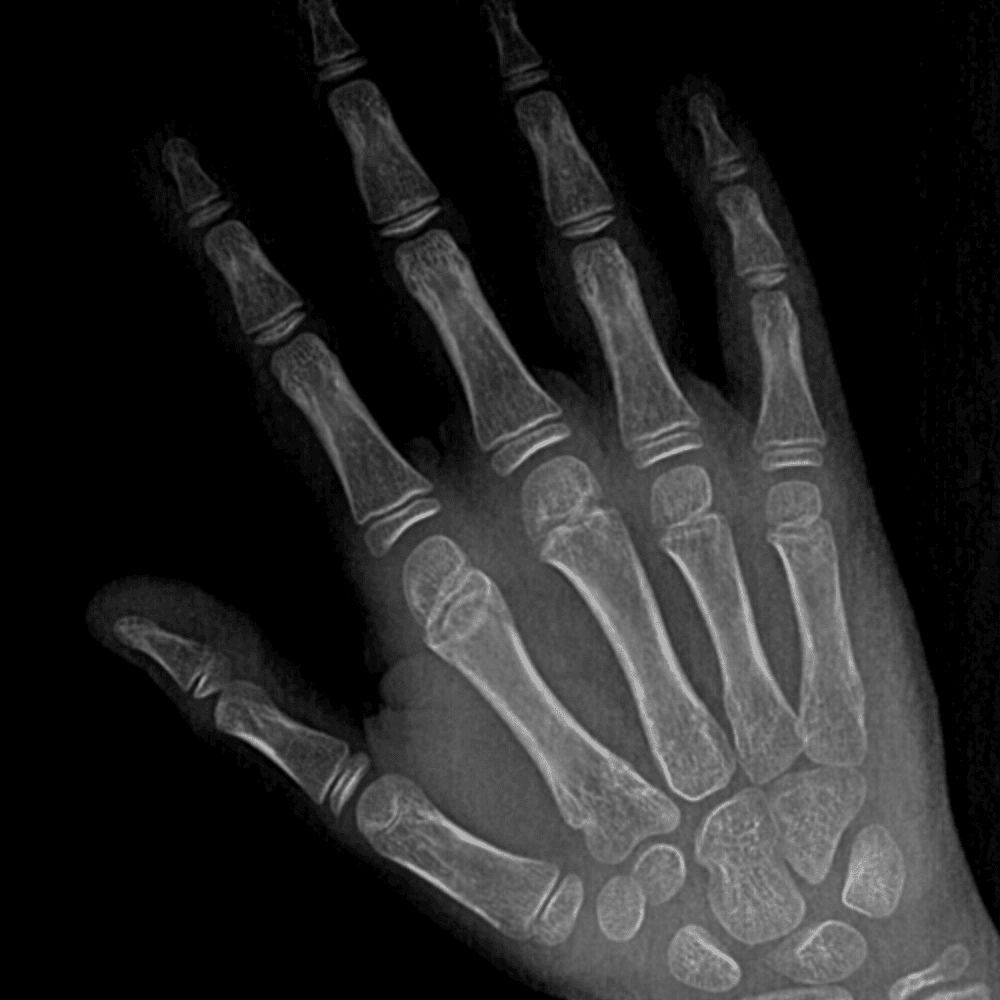

Simulates call by including subtle or difficult cases and some normals.

30 cases